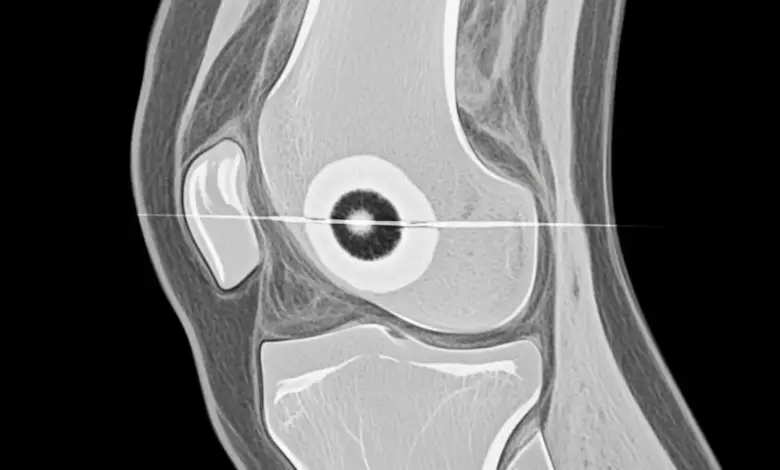

- A radiografia simples pode mostrar o nicho central cercado por esclerose óssea. Mesmo assim, em muitos casos o RX inicial não é conclusivo.

- A tomografia computadorizada costuma ser o exame mais sensível para visualizar o nicho tumoral e localizar a lesão com precisão.